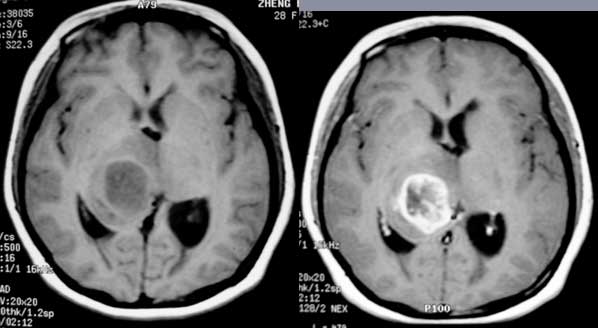

女性,28岁。头痛请会诊

右侧丘脑类圆形等t1,长t2病灶,t1增强明显强化。

考虑:①丘脑胶质瘤可能大。②脑积水。

t1等信号内出现点状高信号,考虑为出血灶,肿块内侧可见弧形低信号,为脑积液影。长t2,其内有混杂信号,周壁强化明显,内不规则强化,生长位置似在右侧丘脑,又似在来源于侧脑室,故脉络丛乳头状瘤不排外。

右丘脑胶质瘤3-4级

右侧丘脑胶质母细胞瘤可能

胶质瘤可能性大,请结合病史排除结核瘤的可能。

右侧丘脑胶质瘤?右侧脑室内的异常信号如何解释?不会是丘脑出血破入脑室?